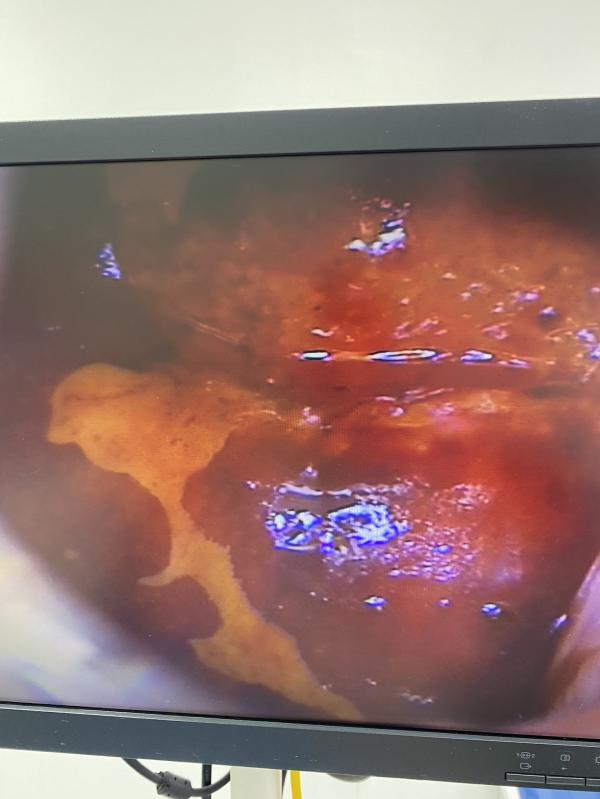

Тем более, когда предстоит сделать процедуру ( вскрытие, биопсия, эксцизия, конт. пластика , установка спирали и тд)